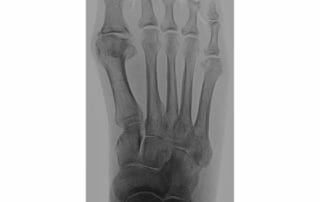

Hallux rigidus – Gelenkverschleiß am Großzehengrundgelenk

Hallux rigidus – ein schmerzhafter Gelenkverschleiß am Großzehengrundgelenk Unsere Knochen und Gelenke sind im Laufe des Lebens hohen Belastungen ausgesetzt. Verschleiß, Verletzungen, Entzündungen, Überbelastungen, Fehlstellungen und daraus resultierende Erkrankungen, [...]